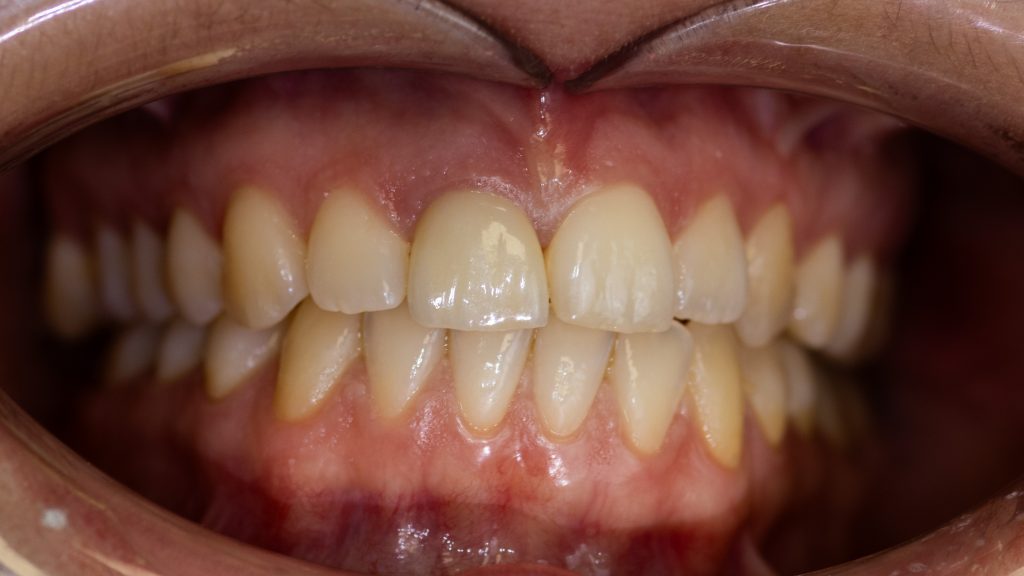

Final Restoration

The future of the aesthetic zone isn’t found in a bottle of bone substitute; it is found in the meticulous preservation of the patient’s own anatomy.